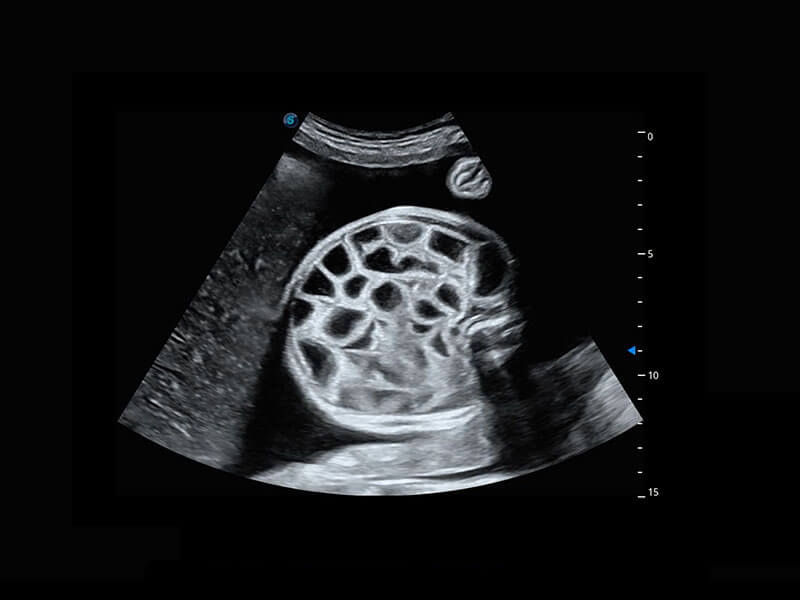

P60搭载宽频带线阵探头、宽景成像、弹性成像技术,为您提供乳腺应用方案。P60支持高频相控阵探头、线阵探头、腹部高频探头、腹部微凸探头等,丰富的探头群搭载敏感的彩色血流成像,适用于新生儿多种脏器检测要求,满足新生儿筛查需求。

新生儿肝血管癌

新生儿脊髓圆锥

新生儿心脏